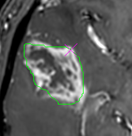

Region of interest (ROI) functions

Three

different ROI methods are available.

Freehand : draws a freehand trace ROI in

active window

The

trace is auto-completed (to form a closed shape) upon releasing the mouse

button. The final ROI can be Moved (pressing right mouse button with cursor

on pink cross).

Polygon (spline) ROI

polygon ROI is initially displayed as a circle with four anchor

points that can be moved to change the shape of the ROI. Additional anchor

points can be added by <ctrl>+ right button click. The whole ROI can be

moved by left-clicking anywhere on the ROI line.